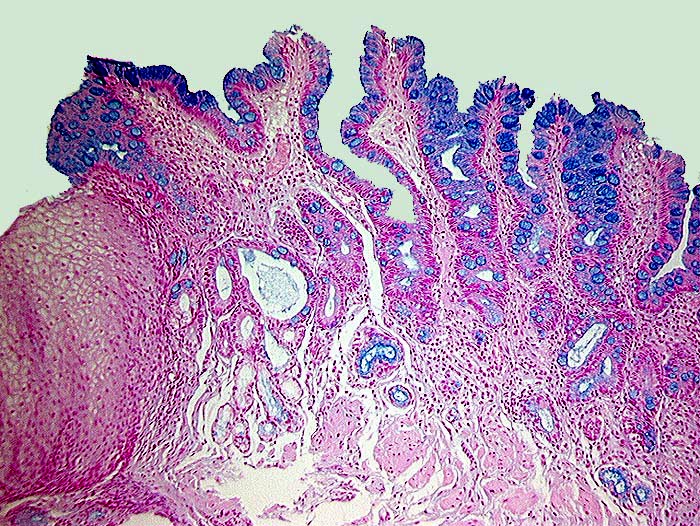

Barrett Schleimhaut ohne intraepitheliale Neoplasie

Zwischen erhaltenen Inseln normaler Ösophagusschleimhaut findet sich spezialisiertes metaplastisches Epithel mit alcianblauen Becherzellen.